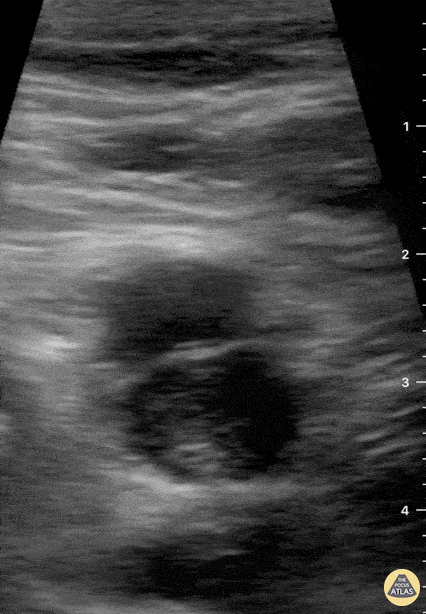

69-year-old male patient with no relevant chronic medical history presents to the ER complaining of two-day right inguinal pain and swollen lower extremity. Directed interrogation revealed one-month subacute dyspnea upon physical effort. Femoral POCUS showed this image. The contractile femoral artery lies superficially and to the left of the screen. The common femoral vein is not fully compressible in this study, and an echogenic thrombus can clearly be identified in its interior. Subsequently, angio CT confirmed a massive bilateral PE, although the patient remained stable and did not require invasive interventions. Dr. Felipe Urriola P. Emergency Unit, Puerto Aysen Hospital. Chilean Patagonia.